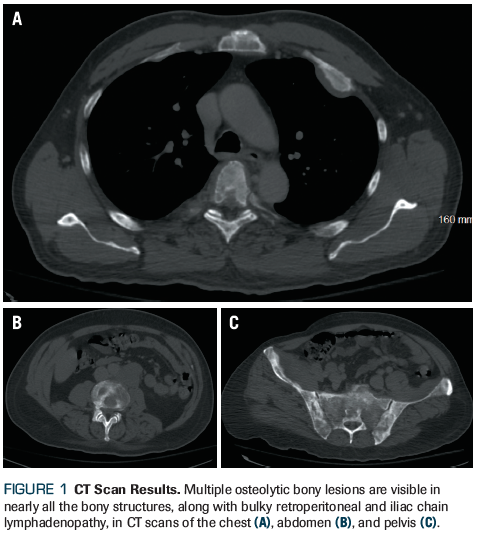

CT scans of the chest, abdomen, and pelvis revealed multiple osteolytic bony lesions in nearly all the bony structures, along with bulky retroperitoneal and iliac chain lymphadenopathy (Figure 1). An MRI of the spine confirmed multilevel spinal metastases and extradural spinal masses at the T5 and L3 levels, causing severe spinal stenosis. A surgical specimen from an internal fixation operation was sent to pathology.